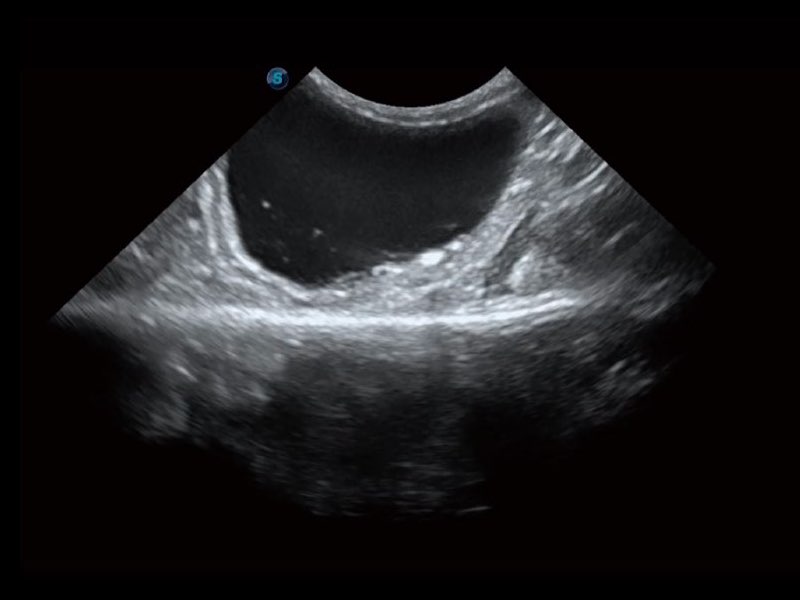

Przy pracach nad aparatem ProPet 60 uwzględniono najważniejsze preferencje i potrzeby weterynarzy, oferując finalnie przystępne cenowo i odpowiednio wyważone połączenie znakomitej precyzji klinicznej, zwiększonej wydajności i przemyślanego przebiegu pracy, niezastąpione w codziennej praktyce weterynaryjnej. Dzięki dostępowi do pełnej gamy głowic HD rozwiązanie to spełnia wszystkie potrzeby w zakresie obrazowania, umożliwiając wykonywanie badań jamy brzusznej, małych narządów, ortopedycznych, badań podczas rozrodu, a nawet badań serca i klatki piersiowej, a to wszystko przy doskonałym stosunku jakości do ceny.